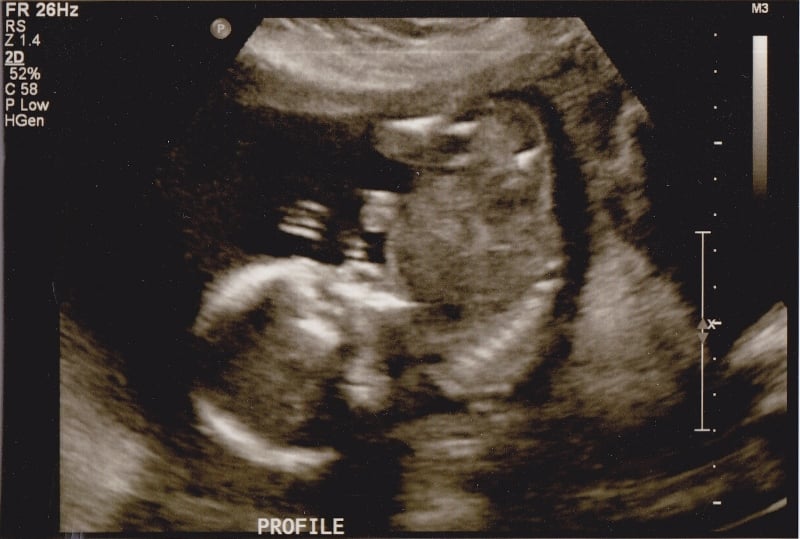

BOY! And most importantly, everything looked good at the anatomy scan. I really didn't care whether I had a boy or girl (this is my first), but I am so excited to know